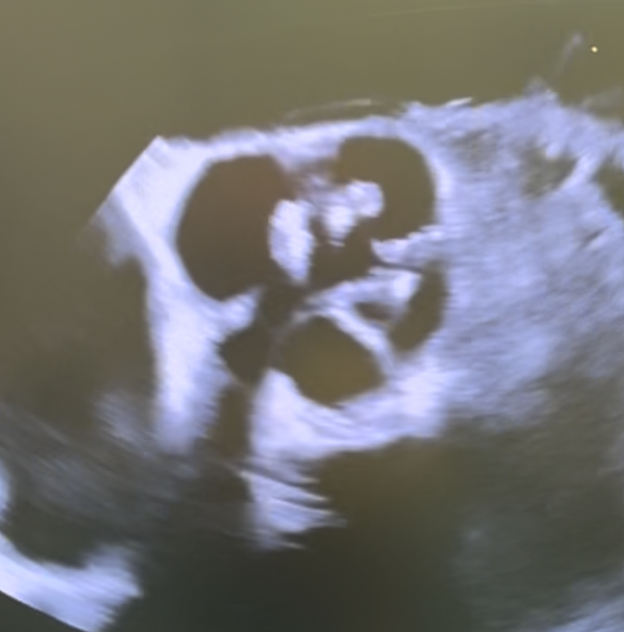

Abstract Body (Do not enter title and authors here): Description of Case: A 58-year-old man presented with progressive fatigue and dyspnea. Echocardiography showed mixed valve disease with severe aortic stenosis (AS), severe aortic regurgitation (AR), left ventricular hypertrophy, and preserved ejection fraction. Coronary angiography was normal. Chest computed tomography angiography revealed a quadricuspid aortic valve (QAV) with severe calcification and aneurysmal dilation of the ascending aorta to 47 mm. At the time of the operation, the quadricuspid valve was functionally bicuspid, with two raphes. An additional cusp was present between the right and left coronary cusps (Nakamura Type 1) with 2 equal larger cusps and 2 unequal smaller cusps (Hurwitz and Roberts Type F). The right and supernumerary cusps, and the left and non coronary cusps, were fused respectively. All cusps were significantly thickened and calcified. The degenerated valve was excised and replaced with a size 27 bioprosthetic valve. The ascending aorta was resected and replaced with a straight graft. Postoperative echocardiography confirmed a low mean gradient and normal function, and the patient had an uncomplicated recovery.